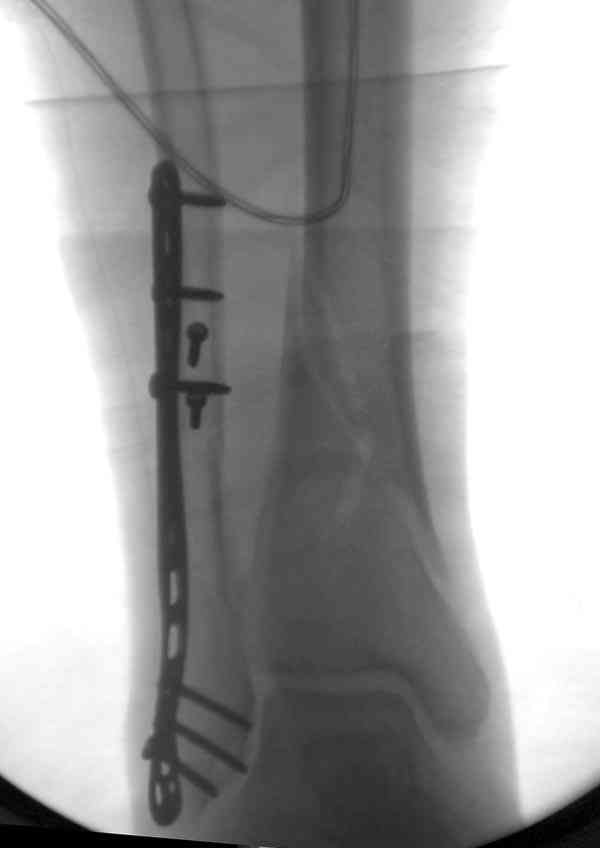

Уже 15 лет в отделении мы активно оперируем свежие переломы ГСС по принципам АО и вполне удовлетворены результатами лечения свежей травмы. В случаях же операций при позднем поступлении или реконструкции после неудачных вмешательств в ряде случаев сохраняется нестабильность ГСС, тенденция к вальгусной деформации. В свежих случаях никогда не приходилось производить шов дельтовидной связки, пластики тоже ни разу не выполнялись. Два примера на снимках.Первый - врач 38 лет, неудачно оперированный в своей больнице с двухлодыжечным переломом, разрывом МБС был повторно оперирован через 8 месяцев. Пытались восстановить длину наружной лодыжки остеотомией, освежили МБС, два месяца функционального лечения без нагрузки на стопу.Сейчас ходит с легкой хромотой, устает к обеду, вальгусное отклонение стопы корригировано супинатором. На Рграммах видны дистрофические изменения латерального эпифиза большеберцовой кости. Первый снимок через 6 месяцев после травмы, операции остеосинтеза болтом-стяжкой, удаленной по причине нестабильности и наличия свища над металлом. Второй снимок через 3 месяца после реконструктивной операции.

Спасибо за вложенную схему , ранее она нам не попадалась.Согласен с Алексеем, что в обоих случаях не удалось восстановить длину фибулы.По вопросу о МБС, в первом случае после 8 месяцев синдесмоз был выполнен плотной рубцовой тканью, которую необходимо было убрать для репозиции фибулы в вырезку и винт действительно был введен с компрессией, во втором случае МБС не открывался и компресии не задавлось.Может дистрофия эпифиза все же следствие 5 месячной нагрузки с нестабильным суставом и компрессии тараном, тк вес пациента достаточно высок. По второму наблюдению необходимо определиться с тактикой, при пронации стопы отчетливо определяется слабость дельтовидной связки-перерастянута ходьбой в нестабильном суставе? Показана ли надлодыжечная варизующая остеотомия?

В том и разочарование у меня, что я пытался на столе удлинить наружную лодыжку, в обоих случаях была выполнена косая остеотомия, варусной гиперкоррекцией стопы создавал удлинение, но скорее всего недостаточное.По первому пациенту у меня вопросов нет, он пока удовлетворен результатом, ведь было много хуже.